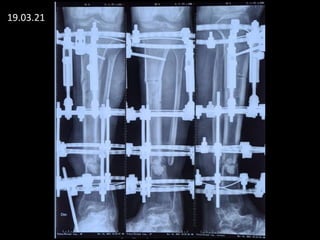

19.03.21